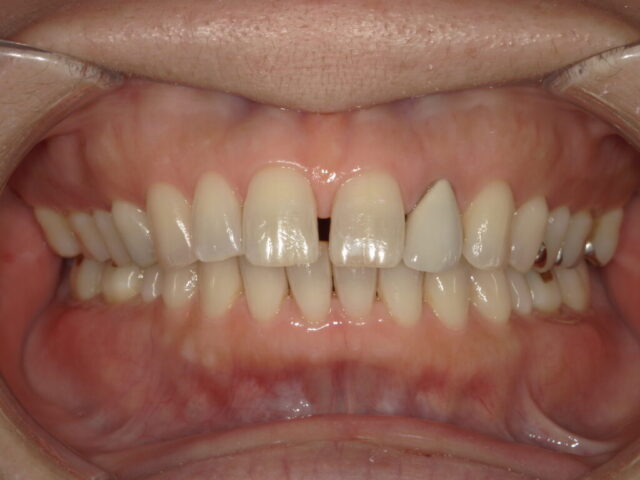

前歯のすき間(正中離開)の改善

成人矯正

| 診断名 | 前歯のすき間(正中離開) |

| 治療期間・回数 | 7ヵ月 |

| 治療方法 | 部分矯正(前歯のみワイヤー矯正)、上唇小帯切除術 |

| 費用 | 220,000円 |

| デメリット・注意点 | 治療開始直後や調整後には、歯が動く際の痛みや違和感が生じることがあります。通常は1週間ほどで慣れていきます。 |